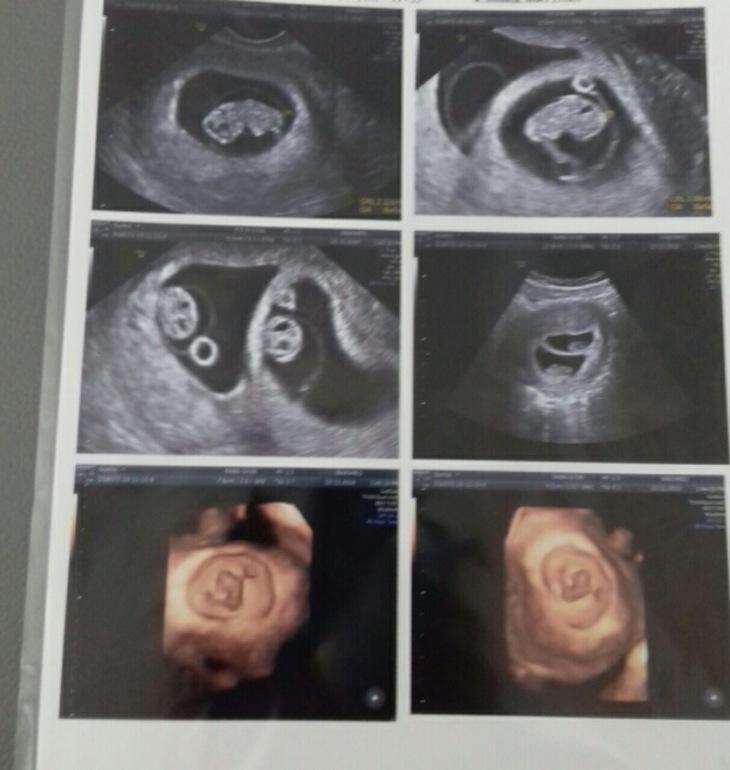

Узи дождалась)))

Так прикольно, видно все :))) Супер :)) Растите здоровенькие :) Пусть все будет хорошо 🤞

Поздравляю! Красивые УЗИ! Растите большими

Как здорово! Поздравляю ! 💐Это какой срок ?

Спасибо! Сегодня 8недель и 4 дня))))